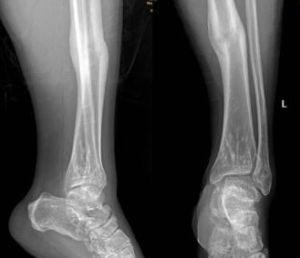

骨骺損傷

骨骺和骺板皆為未成熟骨骼的生長機構,骺板損傷習慣又稱為骨骺損傷(rnjury epiphysis)。小兒骨折中大約15%涉及到骨骺損傷,部分骨骺損傷可造...